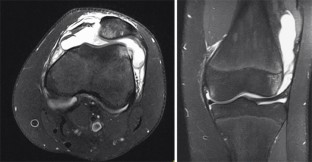

Abb. 1

Abb. 2